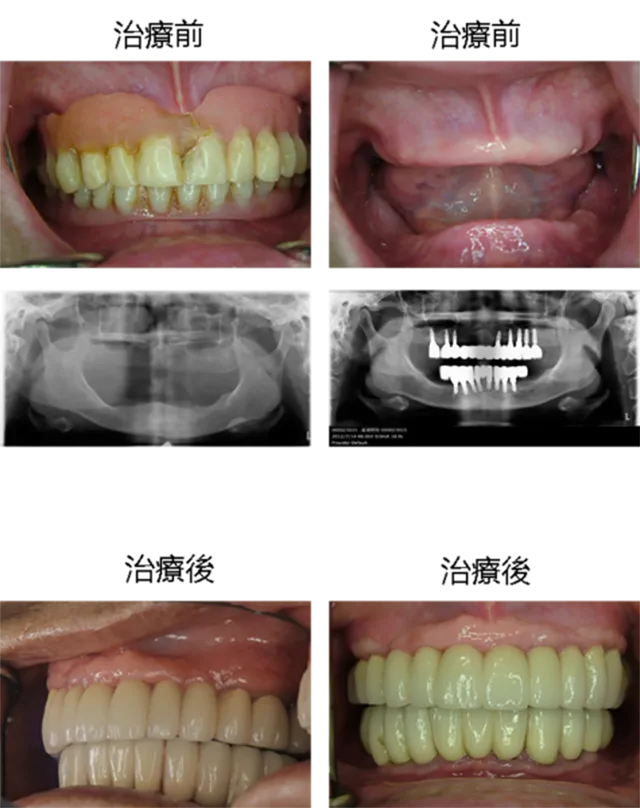

[ 邱小姐植牙案例 ]